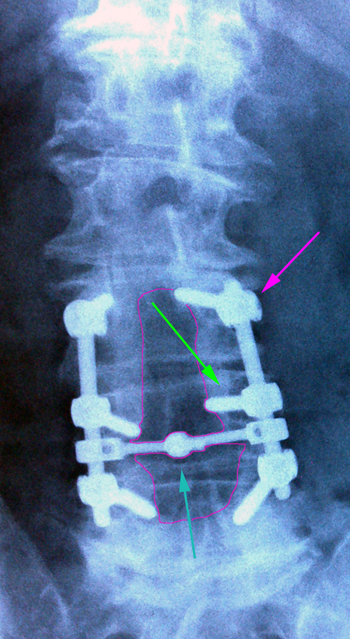

Οσφυϊκή σπονδυλοδεσία Ο3-Ο5. Βίδες στα σώματα των σπονδύλων (πράσινο βέλος) ενωμένες με ράβδους (φούξια βέλος). Συνδετική γέφυρα με κυανό βέλος.Περιοχή της πεταλεκτομής με κόκκινο περίγραμμα. |

Κάταγμα Ο1 σπονδύλου (κόκκινο περίγραμμα), οπίσθια διαυχενική σπονδυλοδεσία Θ12-Ο3. |